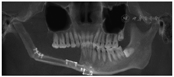

(2)检查:患者颌面部基本对称,右侧颌下区至下唇正中可见1长约14 cm手术瘢痕,双侧颞下颌关节活动度差,重度张口受限,开口度约6.5 mm(图2A),开口型无异常;28、38牙齿口内未见,对应位置牙龈黏膜无异常,37叩痛(±);43—47牙齿缺失,缺牙区牙槽嵴低平,余牙列不齐,口内原腓骨移植术区创口愈合情况可,口腔卫生较差。

(3)诊断:①28高位垂直埋伏阻生、38低位水平埋伏阻生;②下颌骨部分切除腓骨移植术后;③重度张口受限。

(4)治疗:拟全身麻醉下拔除28、38。完善术前相关检查,排除麻醉及手术禁忌证。经患者知情同意并签署知情同意书后,于2020年1月鼻插管全身麻醉下行左侧上下颌埋伏阻生智齿拔除术。术中给予足量药(顺阿曲库铵132 mg),依次辅助使用鸭嘴开口器、钳式开口器及全麻开口器,术中最大被动开口度为10.5 mm(图2B)。37远颊侧联合远中设计角形切口,切开翻瓣,动力系统去骨,T形分牙法分块拔除38;27远中颊侧联合远中设计角形切口,切开翻瓣,去除冠部骨阻力,牙挺完整拔除埋伏阻生28牙齿。拔除的38碎块经拼接检查,显示完整,拔牙窝内光滑,骨壁完整。搔刮拔牙窝,缝合上下颌创口。术中无上颌窦穿孔、下牙槽神经损伤等并发症发生,术后积极给予抗炎、营养等支持治疗,创口愈合情况良好,术后第3天,患者出院,术后1周后复查,术区愈合情况良好,患者未诉特殊不适。